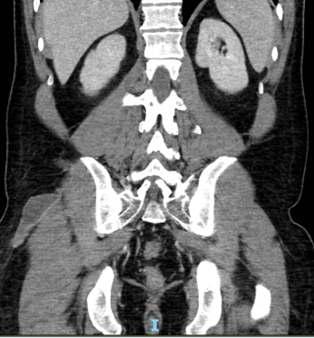

Proteómica aplicada al estudio de la calcificación vascular en la enfermedad renal crónican

Pág 38.